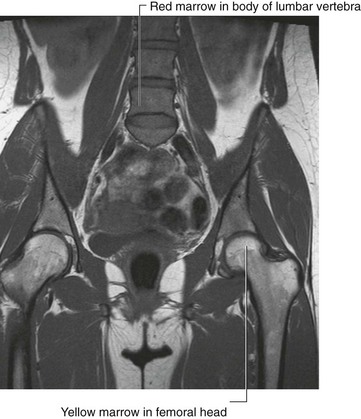

In the clinic Bone marrow transplants

The bone marrow serves an important function. There are two types of bone marrow, the red marrow (otherwise known as myeloid tissue) and the yellow marrow. Red blood cells, platelets, and most white blood cells arise from within the red marrow. In the yellow marrow a few white cells are made; however this marrow is dominated by large fat globules (producing its yellow appearance) (Fig. 1.14).

image

Fig. 1.14 T1-weighted image in the coronal plane, demonstrating the relatively high signal intensity returned from the femoral heads and proximal femoral necks, consistent with yellow marrow. In this young patient, the vertebral bodies return an intermediate darker signal that represents red marrow. There is relatively little fat in these vertebrae, hence the lower signal return.

From birth most of the body’s marrow is red; however, as the subject ages, more red marrow is converted into yellow marrow within the medulla of the long and flat bones.

Bone marrow contains two types of stem cells. Hemopoietic stem cell grafts give rise to the white blood cells, red blood cells, and platelets. Mesenchymal stem cells differentiate into structures that form bone, cartilage, and muscle.

There are a number of diseases that may involve the bone marrow, including infection and malignancy. In patients who develop a bone marrow malignancy (e.g., leukemia) it may be possible to harvest nonmalignant cells from the patient’s bone marrow or cells from another person’s bone marrow. The patient’s own marrow can be destroyed with chemotherapy or radiation and the new cells infused. This treatment is bone marrow transplantation.